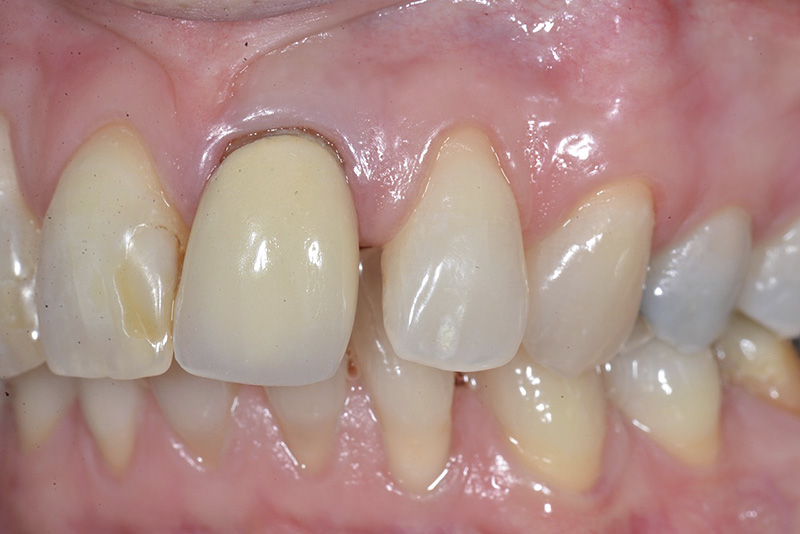

PREMESSA: in seguito all’estrazione dell’incisivo laterale superiore di destra, resasi necessaria per cause batteriche, si decide di affrontare il caso con il posizionamento di un impianto in sostituzione dell’elemento mancante dopo guarigione del sito infetto. Con tecniche rigenerative sia dei tessuti ossei mancanti a causa dell’infezione pregressa, sia dei tessuti gengivali che appaiono inizialmente troppo spostati in alto, si ripristina una corretta morfologia delle parabole (contorni) gengivali e delle papille interdentali (triangoli di gengiva tra due denti vicini).

Vengono utilizzati 2 tipi di provvisori: il primo, cementato ai denti vicini, viene utilizzato dal momento dell’estrazione del dente fino ad impianto osteointegrato (circa 6 mesi); il secondo, avvitato direttamente all’impianto, ha una funzione di prova estetica ma soprattutto di guida per la maturazione dei tessuti gengivali peri-implantari portandoli verso la maturazione completa prima di posizionare la corona finale in disilicato di litio.